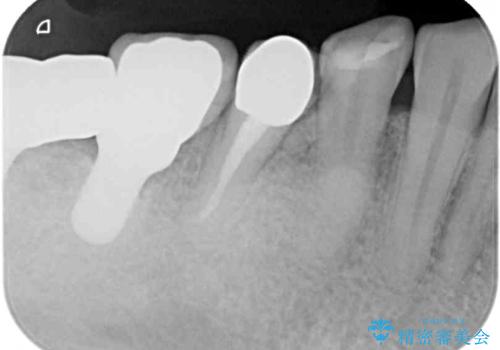

- 強い咬合力により表面のセラミックが剥がれ、裏打ちの金属が見えてしまっていることを気にして来院された患者様です。

仮歯に変えた後、咬合力に耐えることを目的に強化セラミッククラウンにて補綴することとしました。